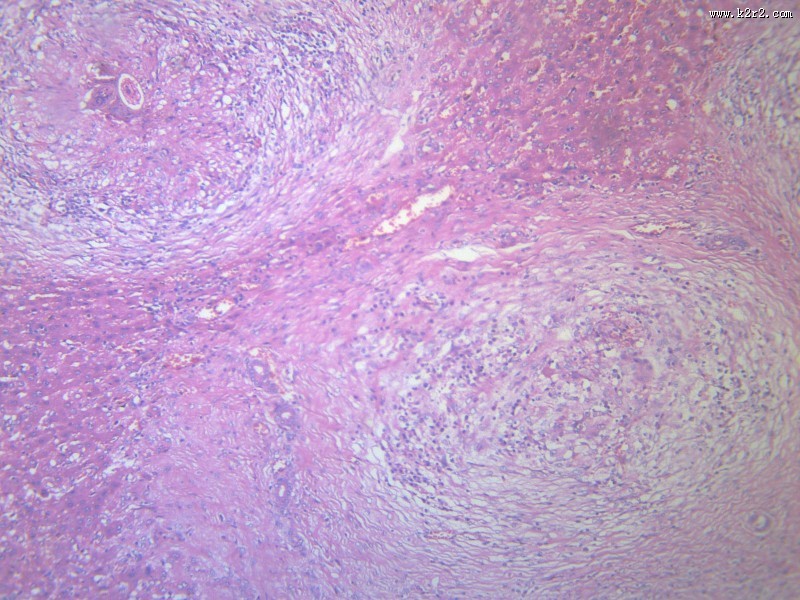

首页 > 其他类别 > 虫卵肉芽肿(12张) > 虫卵肉芽肿 第12张

虫卵肉芽肿 - 第12张